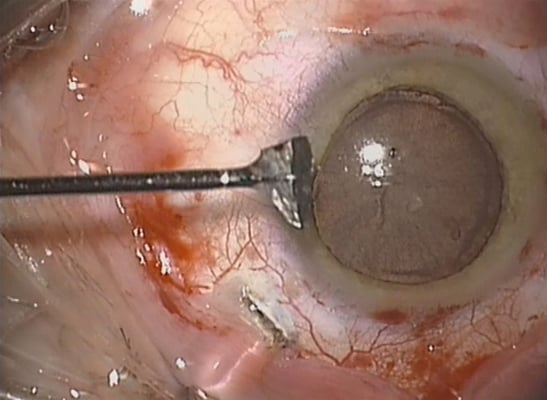

links: großer Defekt der Regenbogenhaut sowie verletzungebedingte Katarakt, rechts: Zustand nach Rekonstruktion der Regenbogenhaut und Ersatz der Linse